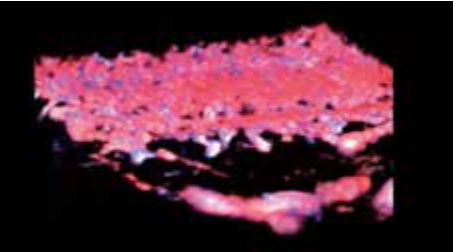

Бешихове запалення

Роздільна здатність зображення, яку забезпечує PLI-2004BX, чітко демонструє підшкірний набряк у місці ураження (рис. 6а). На кольорових зображеннях SMI (cSMI), отриманих за допомогою звичайного лінійного датчика, важко візуалізувати деталі ураження та гіперемію в епідермісі та дермі (рис. 6б). Тоді як вища чутливість cSMI надвисокочастотного датчика легко ідентифікує посилення кровотоку внаслідок сильного запалення (рис. 6в). Крім того, 3D cSMI-зображення, отримане за допомогою PLI-2004BX зі Smart Sensor 3D, одразу відображає всю судинну систему (рис. 6г). Ультрависокочастотний датчик має великий потенціал в дерматології і, як очікується, в повній мірі продемонструє свої видатні можливості з розмежування найдрібніших структур.

г) cSMI зі Smart Sensor 3D з використанням PLI-2004BX

Малюнок 6. Бешихове запалення, виявлене за допомогою PLI-2004BX (24 МГц) ( а, в, г) та PLT-1005BT (12 МГц) (б).